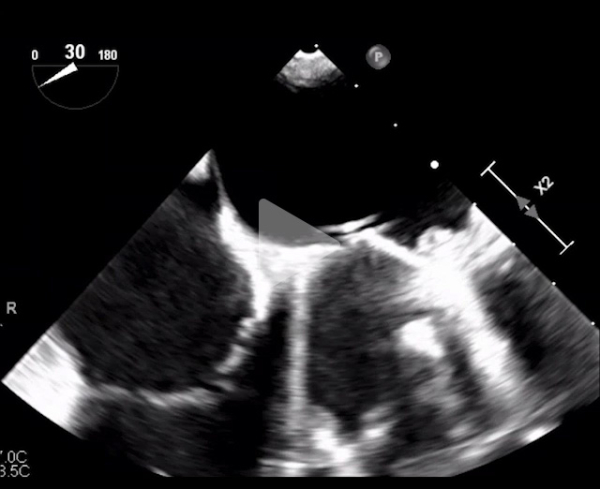

ETT + ETO

Vidéo 1

Vidéo 2